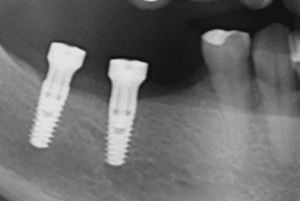

- Dispositif transvissé (bridge ou couronnes contigües). Dans le cas d’une restauration sectorielle sur plusieurs implants, les piliers avec un hexagone externe à leur embase (= pilier avec engagement) -figure 8a- ne peuvent être choisis car ils empêchent de concevoir une restauration prothétique « monobloc transvissée », souvent appelée « direct-implant ». En effet, les implants n’étant jamais strictement parallèles (exemple : figure 11), un dispositif en un seul bloc ne pourra jamais rentrer à fond sur les implants qui risqueraient -si vous vouliez forcer la mise en place- d’être soumis à des contraintes mécaniques délétères (avec au final perte osseuse pouvant mener à la perte d’un implant).